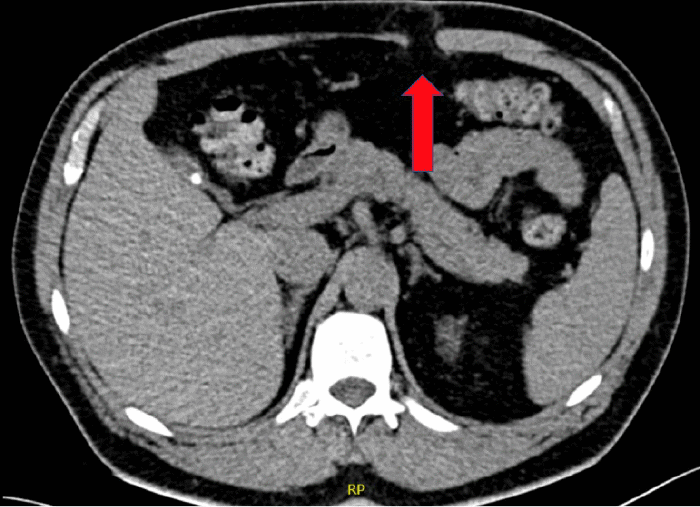

Approximately eight months after PEG tube removal, the patient noticed a bulge in the upper left abdomen that gradually increased in size and became more painful, particularly with coughing or lifting. He denied chronic constipation, cough, or urinary difficulties. Physical examination revealed a reducible bulge, prompting a CT scan of the abdomen and pelvis. The CT scan confirmed a 2 cm incisional hernia containing fat at the left upper quadrant, likely at the prior PEG tube insertion site (Figure 1).

Figure 1. Ventral Hernia on Abdominal CT Scan. Published with Permission

CT scan of the abdomen demonstrating a ventral hernia through a defect in the right upper quadrant